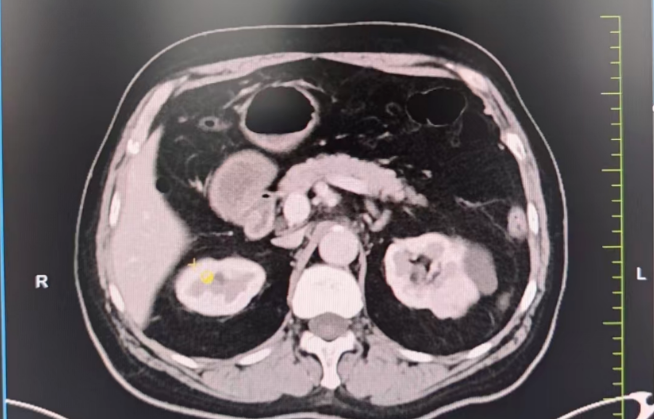

生死抉擇:心臟術(shù)后又遇腎腫瘤,求醫(yī)之路一波三折。3年前,劉大爺因嚴(yán)重冠心病接受了心臟搭橋手術(shù),并置換主動脈瓣生物瓣。術(shù)后長期服用阿司匹林抗凝,病情相對穩(wěn)定。然而半年前,一次體檢發(fā)現(xiàn)他的左腎長出一枚直徑3×2cm的腫瘤,需盡快手術(shù)切除。

難題接踵而至 1.保腎難題:劉大爺保腎臟意愿強烈,需行高難度的腹腔鏡腎部分切除術(shù),但因劉大爺心臟術(shù)后長期口服阿司匹林抗凝,對于保腎手術(shù)增加了出血風(fēng)險高。2.心臟高風(fēng)險:多家醫(yī)院評估后認(rèn)為,劉大爺心臟功能較差(心功能Ⅱ級),術(shù)中可能出現(xiàn)心衰、血栓等致命風(fēng)險,拒絕手術(shù)。

兩大難關(guān),精準(zhǔn)突破1. 心臟“護航”計劃:由醫(yī)院副院長、心血管中心主任隋立有牽頭,調(diào)整抗凝方案:術(shù)前7天停用阿司匹林,改用低分子肝素橋接,降低術(shù)中出血風(fēng)險。優(yōu)化心臟功能:控制血壓,確保心功能穩(wěn)定在Ⅱ級。術(shù)中全程心電監(jiān)護,實時調(diào)控血壓、心率,預(yù)防心肌缺血。 2. 保腎“微創(chuàng)”方案:泌尿外科團隊在張寶主任的帶領(lǐng)下決定采用后腹腔鏡下腎部分切除術(shù),最大限度保留正常腎組織,術(shù)中控制出血量<50ml,手術(shù)時間縮短至1.5小時,大幅降低心臟負荷,術(shù)后轉(zhuǎn)入重癥監(jiān)護室(ICU)密切監(jiān)測,24小時專人監(jiān)護心肺功能。